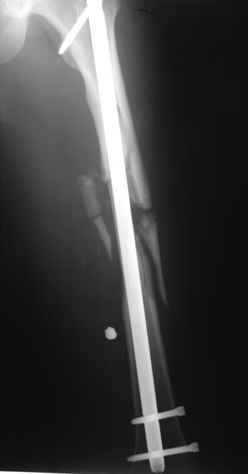

В приложении пример огнестрельного ранения бедра, оперированного на 2 сутки после ранения.

Штифтование было выполнено только на вторые сутки по причине задержки перевода из другого госпиталя, АБ профилактика была начата в другом учреждении, с момента госпитализации пациента к ним. Входное пулевое отверстие и зона введения штифта зажили первичным натяжением.

В конце 90-ых попалось несколько статей по nail exchange procedures in treatment of posttraumatic osteitis и решился попробовать на огнестрельных переломах, которые до этого лечил по полной схеме:расширенный дебрайдмент+ внешняя фиксации+промывные системы с антибиотиками и без антибиотиков в промывной среде. Всё заканчивалось длительной госпитализацией, плохими функциональными результатами( страдала функция колена), необходимостью повторной хирургией - отсроченная внутренняя фиксация переломов, длительной реабилитацией. На гвоздях процесс пошел лучше: остеомиэлитов не было и больные мобилизовывались быстрее.

Единственно что наблюдал - замедленная консолидация, судя по серийным Рг граммам. В приведенном случае прии вялом мозолееобразовании сделал ошибку, решившись динамизировать гвоздь - перелом сросся со значительным укорочением бедра - повторная хирургия по удлинению бедра и проксимальным запиранием, больной мобилизован и вполне доволен(кстати заметить больной с ВИЧ инфекцией - изначально скомпрометированный иммунитет и несмотря на это, всё прошло без костной и мягкотканной инфекции.